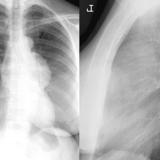

Case 8a Thymoma PA

Date: 03/27/2009

Views: 9457

Case 8b Thymoma Lat

Views: 14097